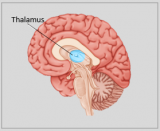

A neuroanatomia é o ramo da anatomia que estuda a anatomia do sistema nervoso, ou seja, a estrutura, a função e a organização do sistema nervoso. O sistema nervoso é um dos sistemas mais complexos do corpo humano e inclui o cérebro, a espinal medula, os nervos periféricos e os gânglios nervosos. A neuroanatomia preocupa-se com a forma como estas estruturas estão ligadas entre si, como os sinais são transmitidos entre as células nervosas e como as diferentes partes do sistema nervoso trabalham em conjunto para controlar as funções corporais e cognitivas. Os neuroanatomistas utilizam técnicas de imagiologia avançadas, como a ressonância magnética (MRI), a tomografia por emissão de positrões (PET) e a microscopia para visualizar as estruturas e funções do sistema nervoso.